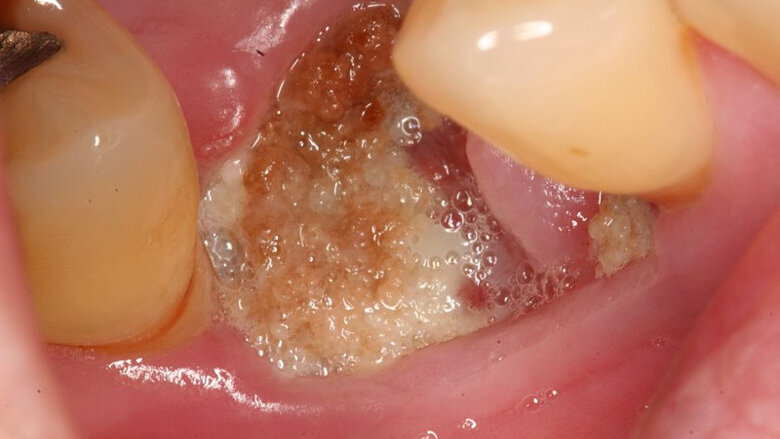

The 85-year-old female patient presented with osteoporosis and a dental implant placed a year before that was causing her pain. The researchers’ examination revealed exposed and dead bone, swelling, redness and discharge around the implant site. The patient was first provided with a conventional treatment of chlorhexidine rinsing, antibiotics and analgesics, but experienced no improvement after three months. She was then given weekly injections of teriparatide—a hormone that promotes bone formation—for eight weeks and monitored for any side effects. During treatment, they tested the initial levels of C-telopeptide (CTx), a compound that is an indicator of bone turnover, and osteocalcin, a protein involved in bone formation.

The clinicians detailed numerous improvements seen throughout the treatment period and six-month follow-up. Notably, the dead bone disappeared, the wounds healed, the CTx level improved from 121 pg/ml to 294 pg/ml, and the osteocalcin level increased from 12.8 ng/ml to 18.5 ng/ml, all of which correspond to an increase in bone formation.